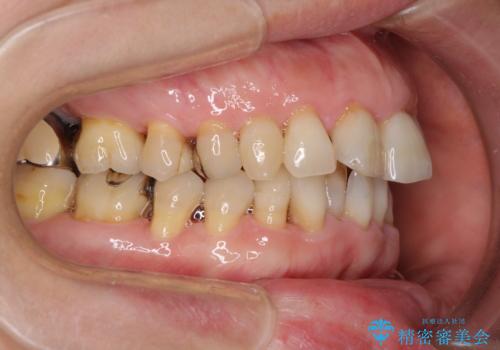

- 近医にてインプラント治療を行った後に矯正治療を希望され、来院された患者様です。

口元の突出感とデコボコが気になっているとのことでしたが、インプラントが既に3本埋入されていたため、抜歯矯正による口元を引っ込めることができない状況でした。

近医での歯周病治療の影響でブラックトライアングルが発現していたため、IPR(歯と歯の間を削る)で隙間を改善しつつ、インプラントを固定源に歯列全体を後方へ移動させることとしました。

インプラントは矯正治療では動かすことができないため、インプラント治療を行う前に矯正治療を行う意思があるのかを確認します。

特に出っ歯などで抜歯矯正となる場合には、インプラントが邪魔になることがあるので注意する必要があります。